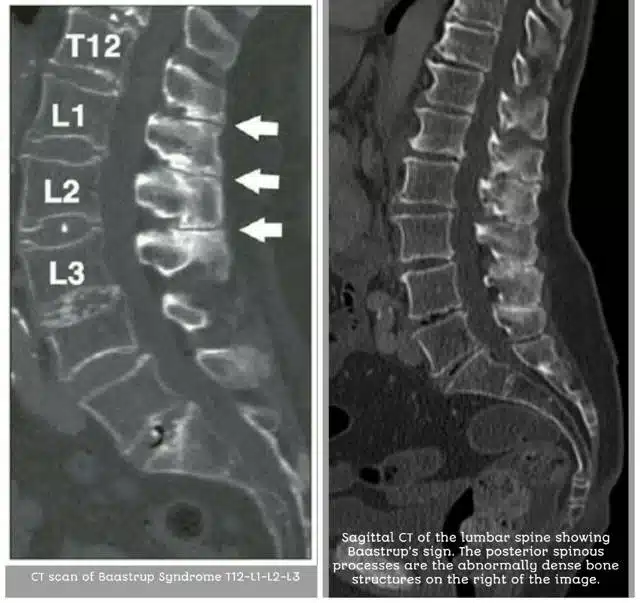

Cuando la enfermedad de Baastrup está más avanzada con una simple radiografía se puede llegar al diagnóstico. Otra prueba útil es el TAC en el que podremos apreciar la insuficiencia del ligamento interespinoso y los cambios que se producen en el hueso debido al roce.